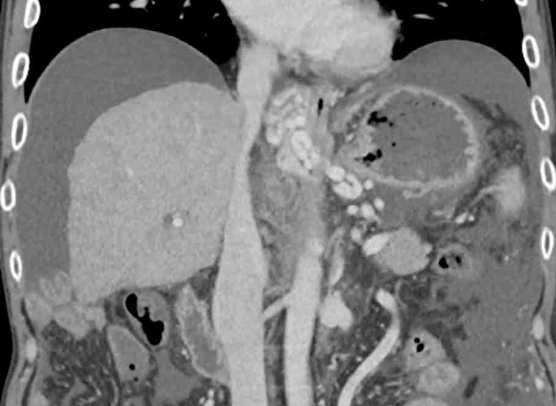

CT: Large amount of ascites, esophageal varices

• 식도위내시경 상에서는 식도 내부에 구불구불하게 돌출된 정맥류가 확인되며, 복부 CT상에서도 식도 부근에 조영 증강된 정맥류 소견이 관찰된다. 추가적으로 복부 CT에서 다량의 복수 또한 관찰할 수 있다.